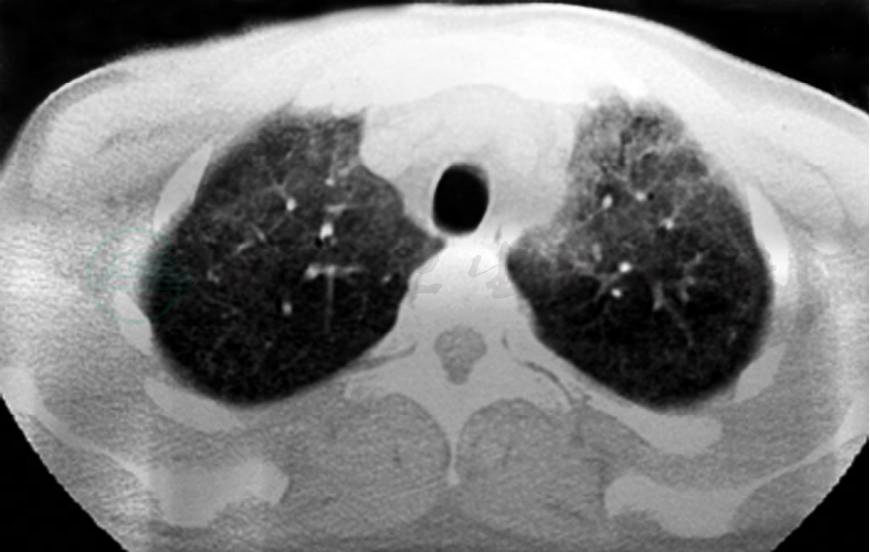

青年男性患者,农民,未婚,既往体健,否认呼吸系统疾病及其他慢性疾病史,无饲鸽、发霉物质接触史。1个月前受凉后出现发热,伴寒战,最高体温达40℃,呈稽留热,伴咳嗽、少许白痰,呼吸困难,活动后明显,无夜间憋醒,就诊于当地医院行胸部CT检查示:双肺对称的弥漫性分布的磨玻璃影(如图1、图2),予抗感染治疗,先后静脉滴注红霉素、头孢哌酮-舒巴坦半月余(具体用法用量不详),体温较前有所下降,但未降至正常,咳嗽、呼吸困难症状未见明显缓解,为求进一步诊治来诊。病来无胸痛、咯血,无腹痛、腹泻,无头痛,头晕,精神状态差,饮食睡眠差,二便可,近一月体重减轻约8kg。

图1 胸部CT

图2 胸部CT